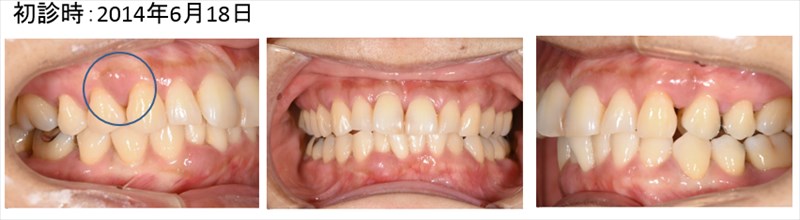

この症例は重症の歯周病の患者さまを1本たりとも歯を抜かず安定している症例です。

歯茎が腫れあがり膿をもっていました。青丸の部分です。全顎的に重度歯周病です。

骨が平坦になり歯ブラシのしやすい形態になって今年も安定しています。術後4年、問題なく1本も歯を失っていません。

術前の腫れは全く見られません。